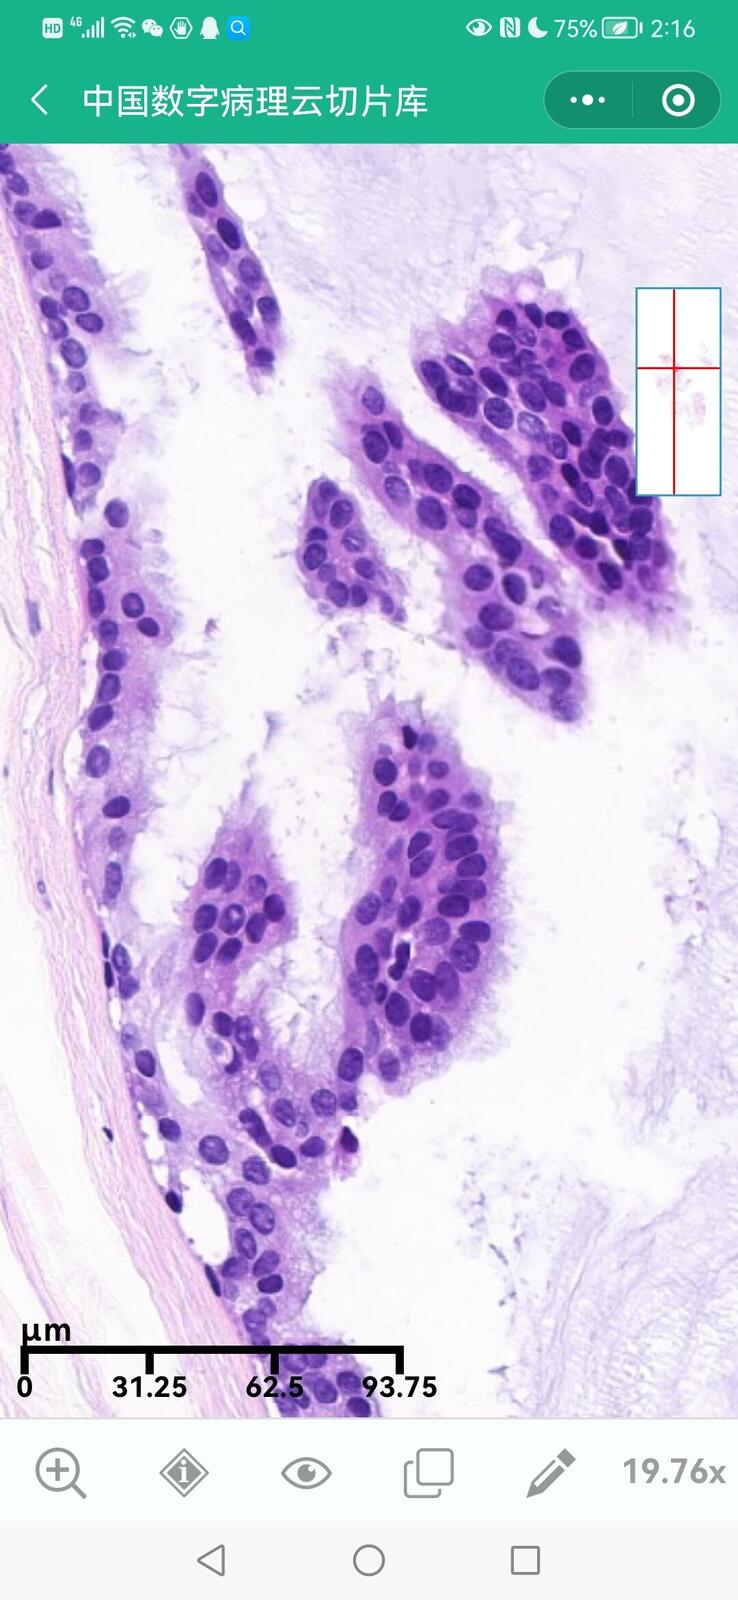

乳腺分泌性癌(29岁)